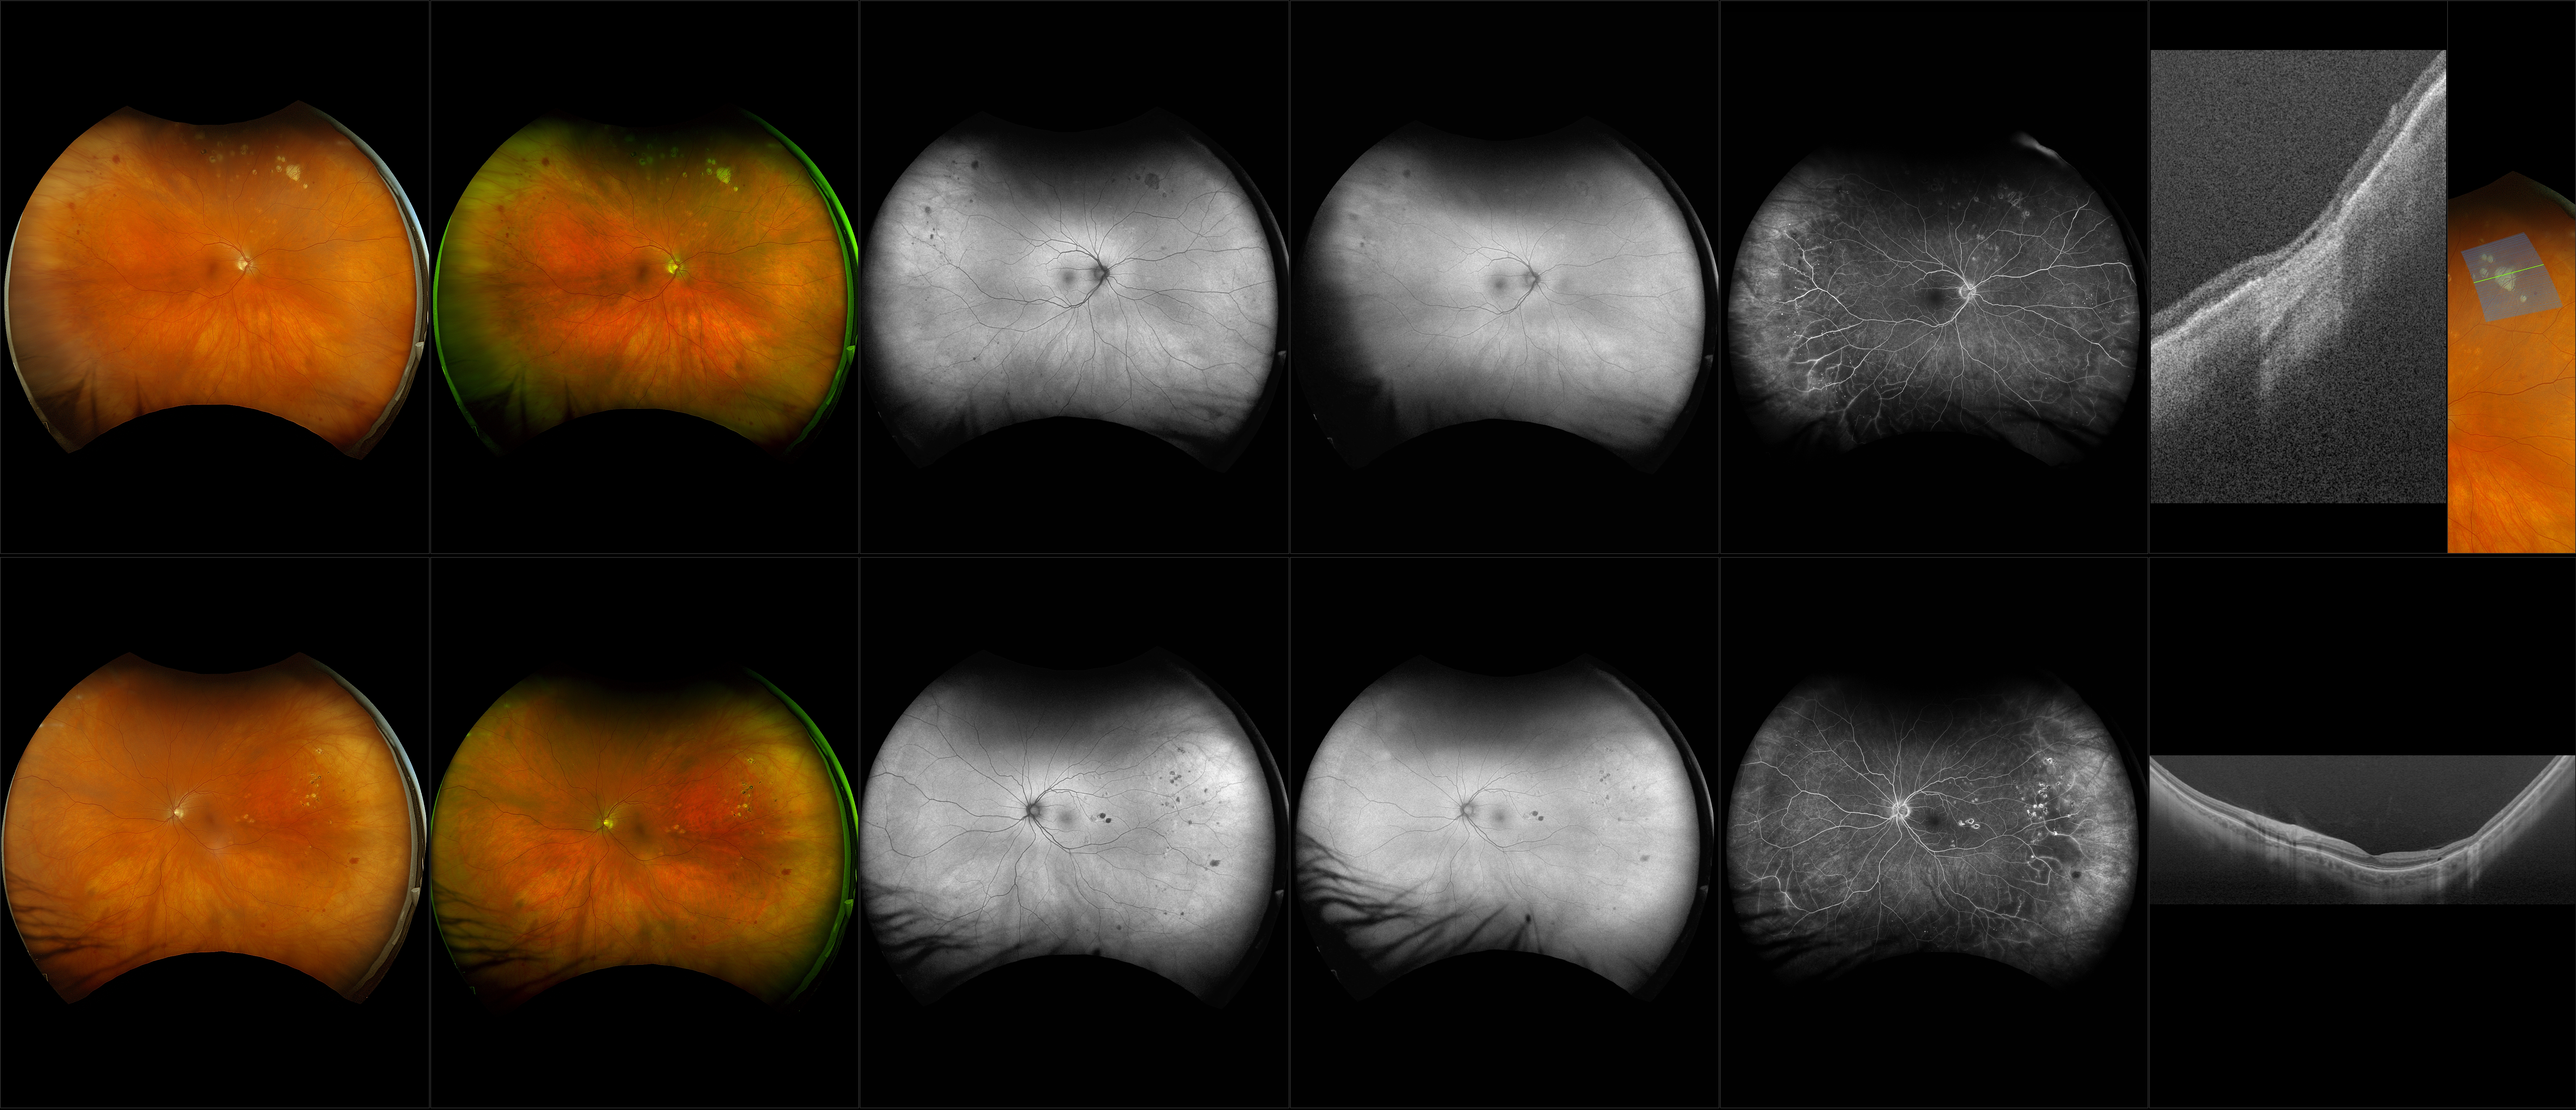

Silverstone - Moderate Nonproliferative Diabetic Retinopathy (NPDR) (OU) - RG, RGB, AF, BAF, FA, OCT - Line, UWF Line, Raster, Retina, Navigated Volume

Diabetic eye disease is a complication of Diabetes Mellitus. Diabetic retinopathy is often detected as a complication, and it presents by affecting small blood vessels in the eye due to blockage or leakage. Over time, blood vessels can present as microaneurysms or hemorrhages or fluid (exudates). The number and severity of affected vessels determine the grade or retinopathy. There are 2 forms, nonproliferative (NPDR) and proliferative (PDR).